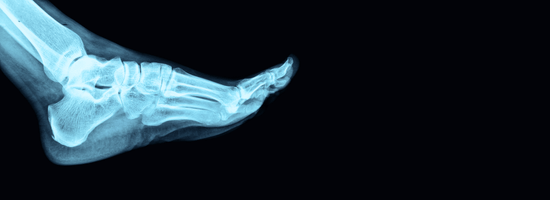

Foot and Ankle Pain

Foot and ankle problems can interfere with everything from daily routines to your ability to stay active. Whether you’re dealing with a sports injury, chronic pain, or mobility issues, expert orthopedic care can get you back on your feet—stronger and pain-free.

Our orthopedic foot and ankle specialists offer comprehensive care for a full range of conditions, using the latest techniques in diagnosis, treatment, and rehabilitation.